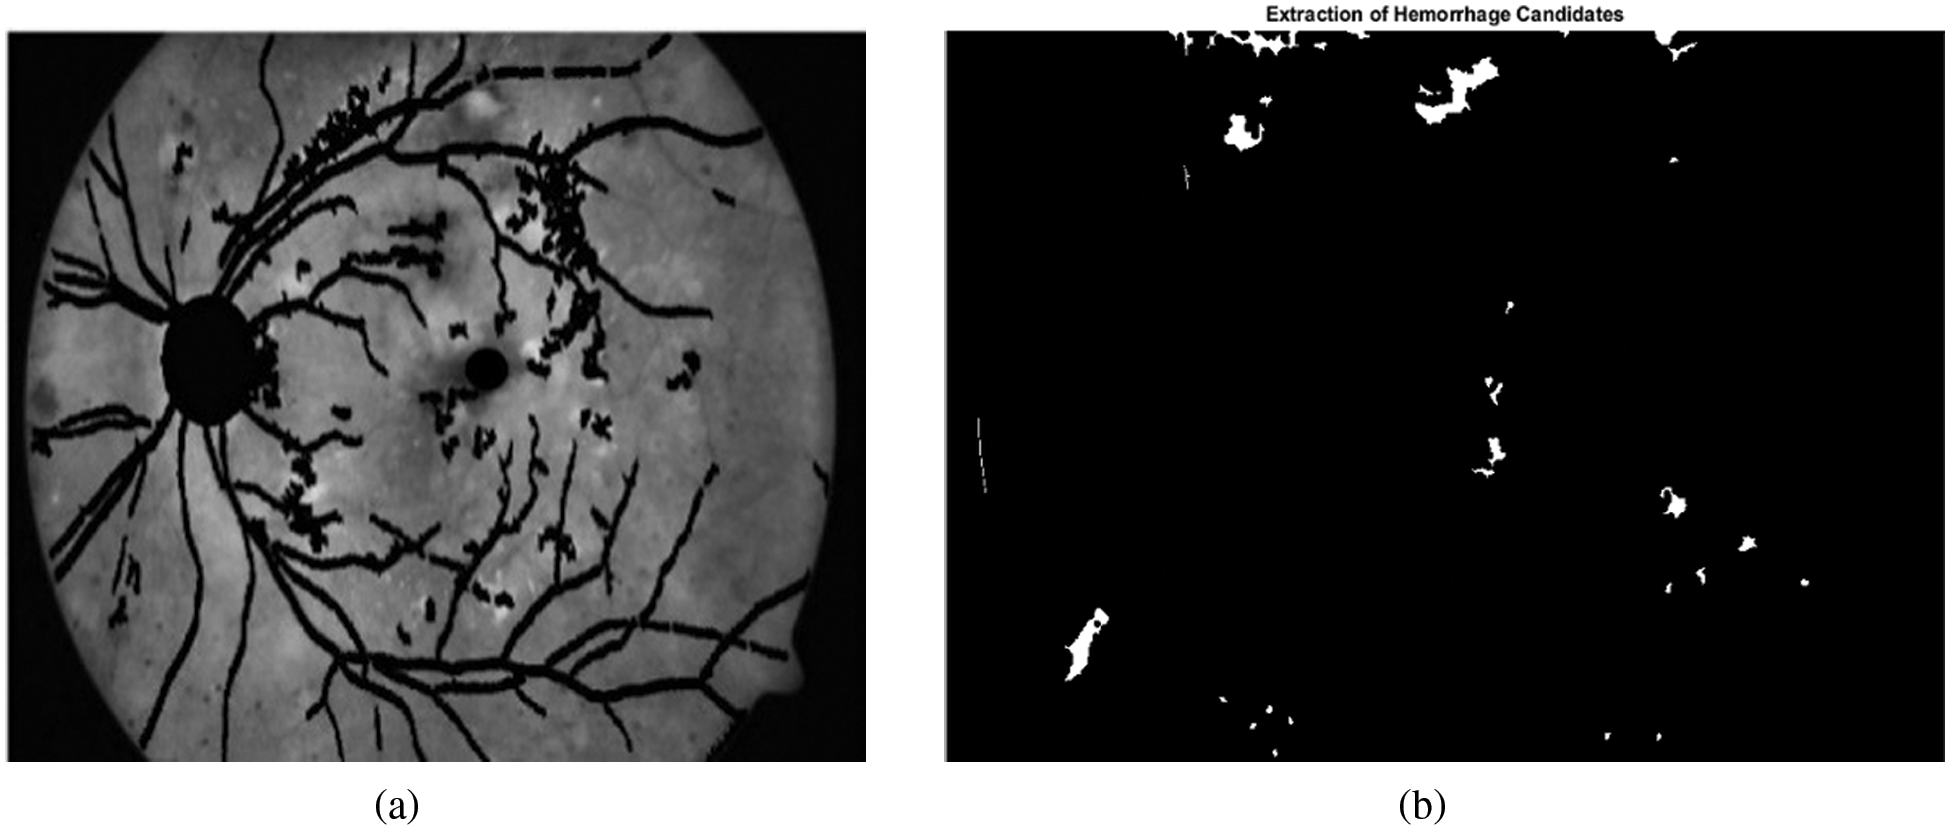

Here A is the input image in green channel and SE is symmetrical disc structuring element with radius 12. Fig. 5b shows the binary image of the hemorrhage candidates in white color and the background in black color.

Figure 5: Extraction of candidate hemorrhages. (a) Retinal image after masking blood vessels, optic disc and fovea. (b) Candidate hemorrhages